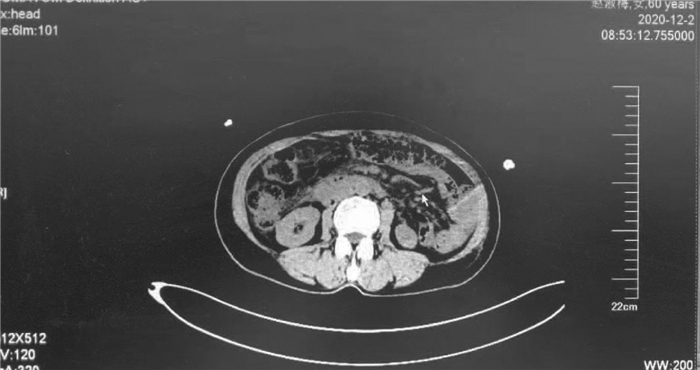

Massive hemorrhage caused by total gastrointestinal varices and recurrent heterotopic varices due to portal vein tumor: A case report

Qin LIU, Heye LIANG

2021, 37(10): 2414-2416. DOI: 10.3969/j.issn.1001-5256.2021.10.032

Abstract(752) HTML (344) PDF (3571KB)(53)

Abstract: